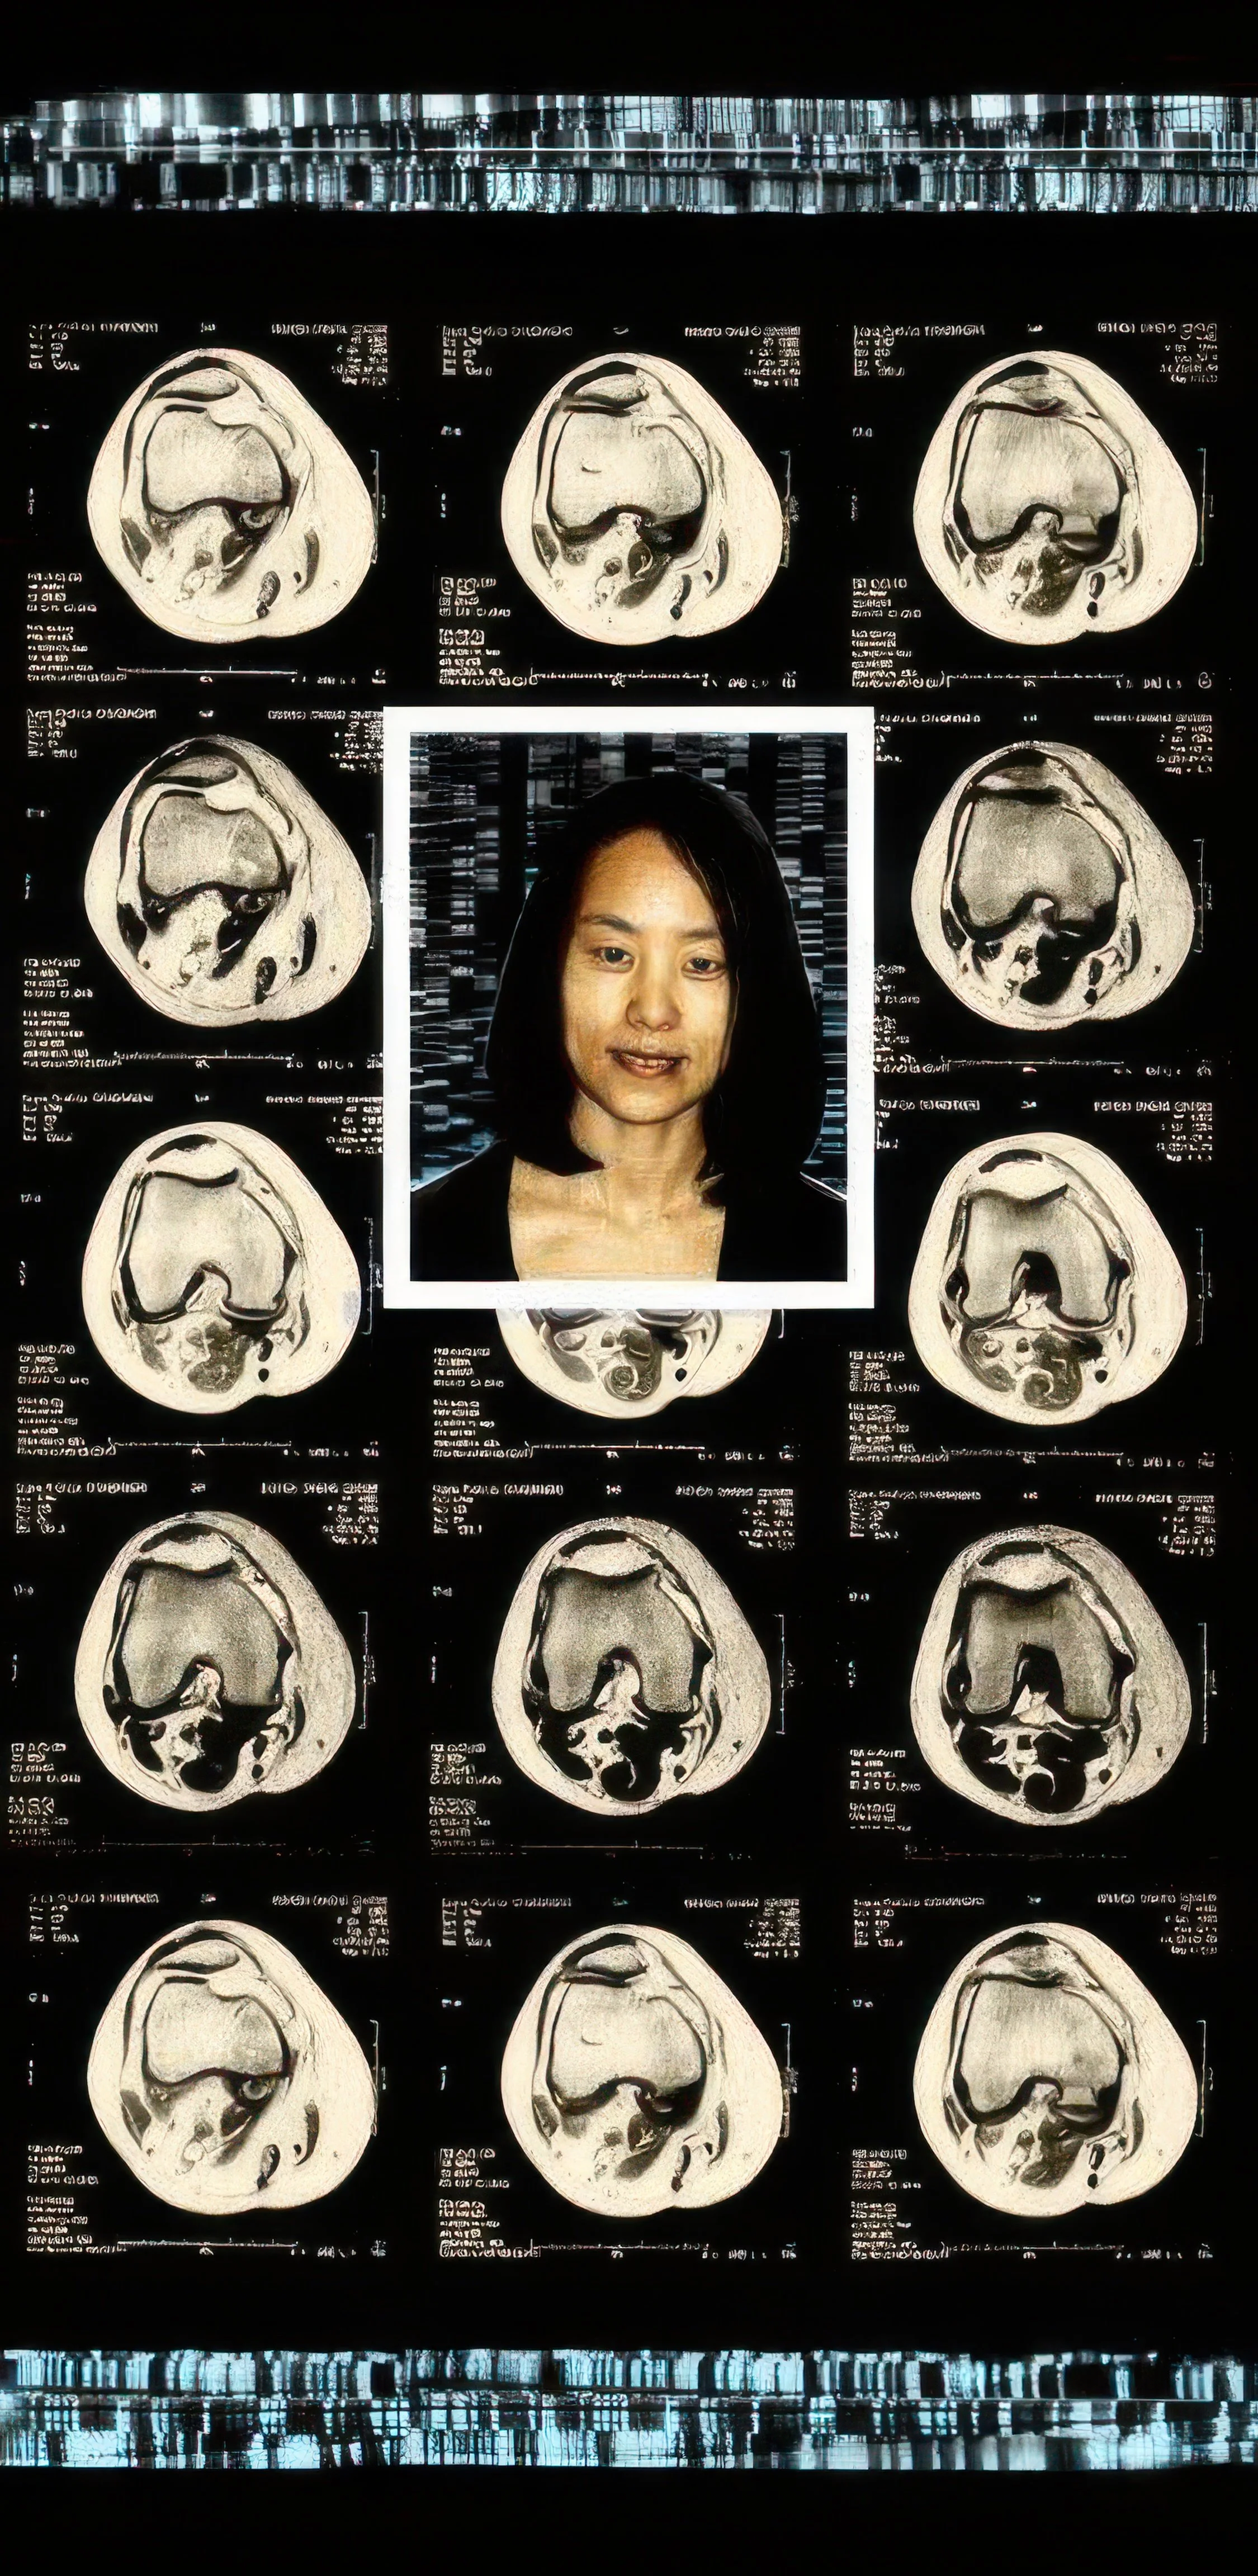

Comprising eight 47” x 23” backlit Plexiglas panels, each work features a portrait, often of individuals from diverse racial, ethnic, and cultural backgrounds. Surrounding these portraits are embedded CT scans, MRIs, and DNA sequencing gels. These medical images, reimagined as expressive symbols, evoke biological inheritance, invisible histories, and interior experience rather than clinical diagnosis.

Used metaphorically, DNA strands suggest ancestral continuity; CT scans and MRIs hint at the unknowable workings of body and psyche; ghostly anatomical forms recall trauma, resilience, and emotional scars. By pairing portraiture with interior imaging, the series questions how we perceive identity. Are we defined by surface appearance—skin, gender, dress—or by memory, genetics, and lived medical experience? Can scientific data be truly neutral, or does it reflect cultural bias and interpretation?

Asian 47” x 23”47” x 23”